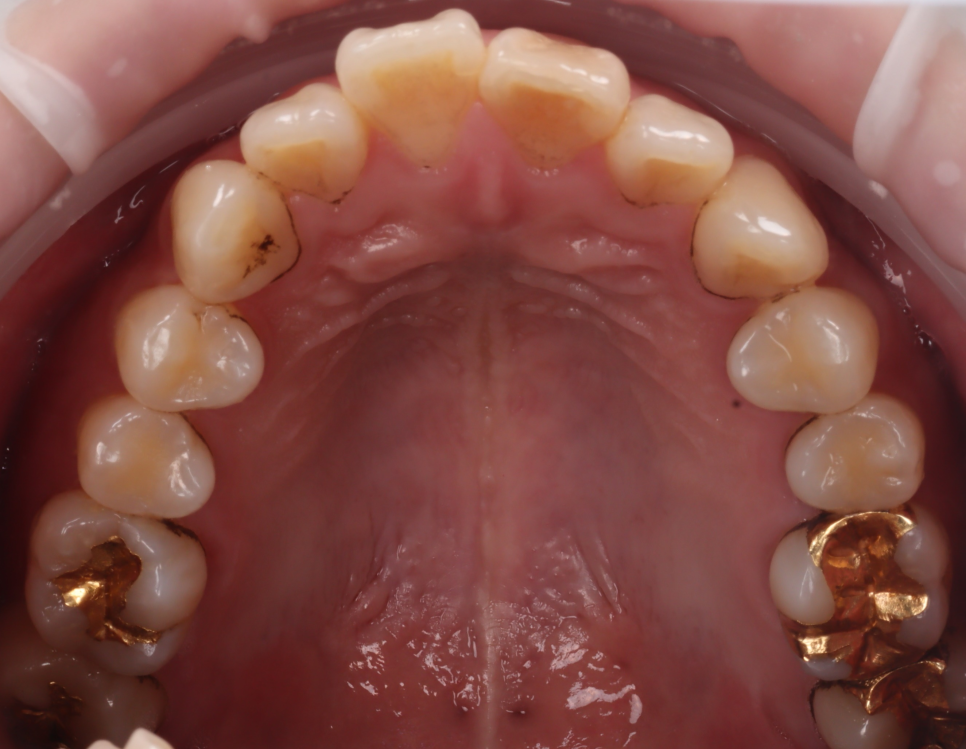

겉으로 보이는 표면에

착색이 도드라진 상태였고,

치아의 안쪽 면, 씹는 면 부근에

브라운 계열의 색소가 고착되어 있었습니다.

촬영일 : 250607